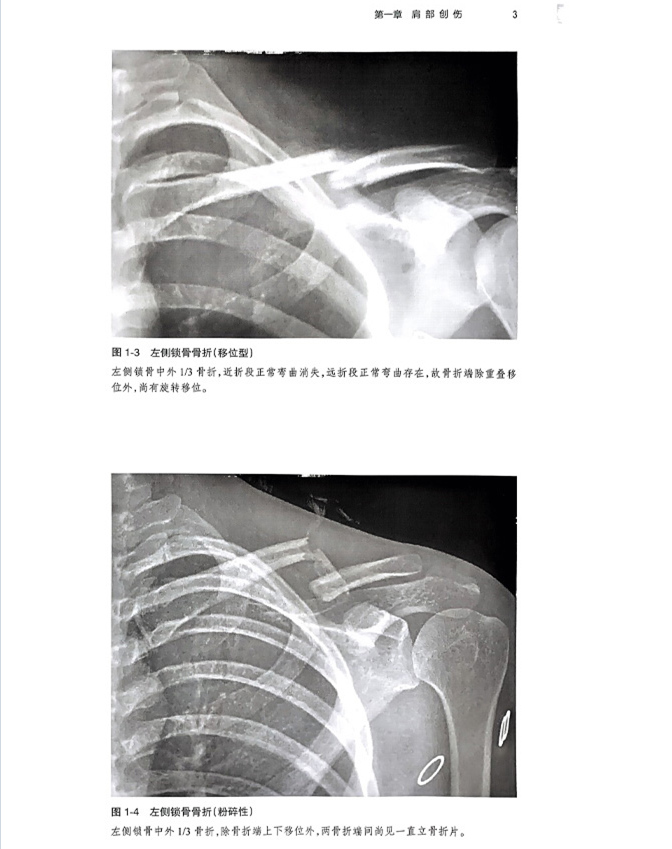

本书是一本系统全面介绍骨关节创伤X线诊断的图谱专著。全书共十六章,前十五章每章基本按创伤类型、诊断要点和鉴别诊断体例编写,最后一章介绍常见骨关节创伤后遗症及并发症。书中共选用1270幅X线照片图,约760个病例,所选图片和病例均具有代表性,可使读者对各部位、各类型的骨关节创伤及其后遗症和并发症有进一步认识,从而提高诊断水平。本书主要供骨科医生、影像科医生使用。